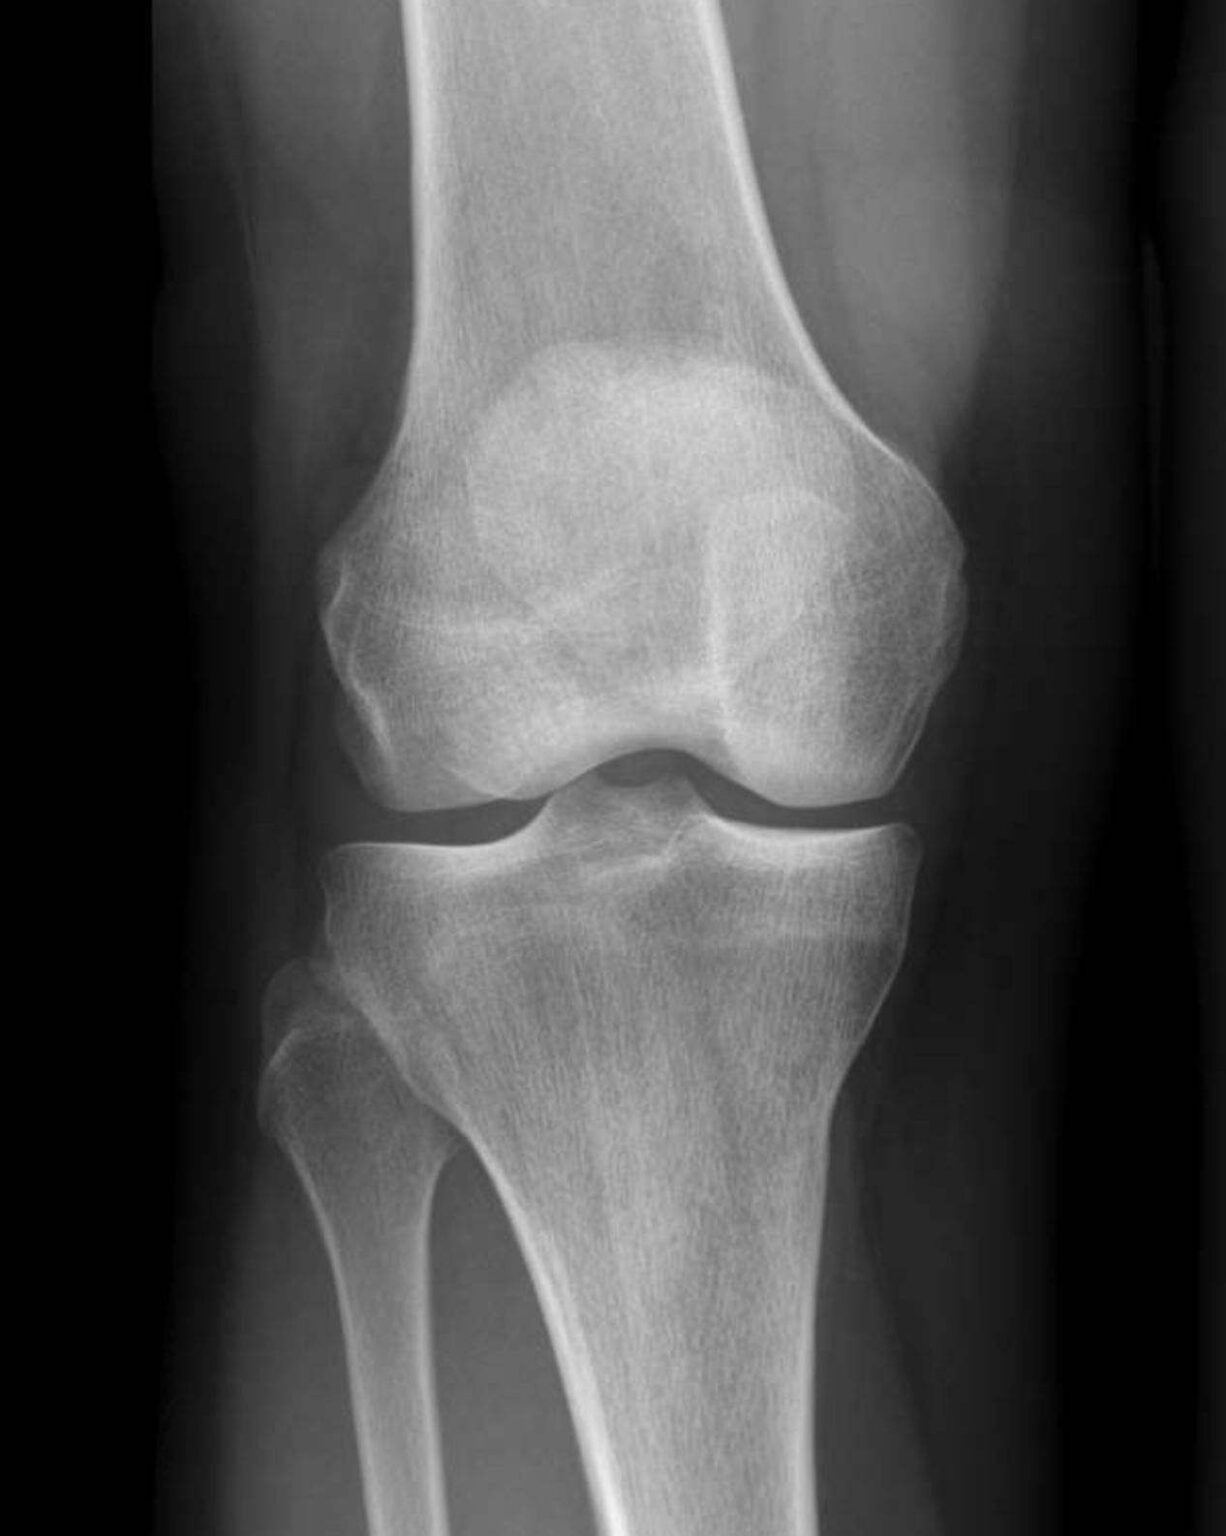

Röntgenfoto Knie Met Vocht. Artrose van de knie Slingeland Ziekenhuis Ook kan het vocht uit je knie verwijderd worden met behulp van aspiratie Een röntgenfoto kan uiteindelijk een artrose in de knie aantonen: artrose geeft röntgenologisch een versmalling van de gewrichtsspleet.

Vocht in de knie Alles wat je moet weten & 3 Praktische oefeningen. Een röntgenfoto kan uiteindelijk een artrose in de knie aantonen: artrose geeft röntgenologisch een versmalling van de gewrichtsspleet. Na het onderzoek kleedt u zich weer aan en krijgt u te horen of de röntgenfoto gelukt is.